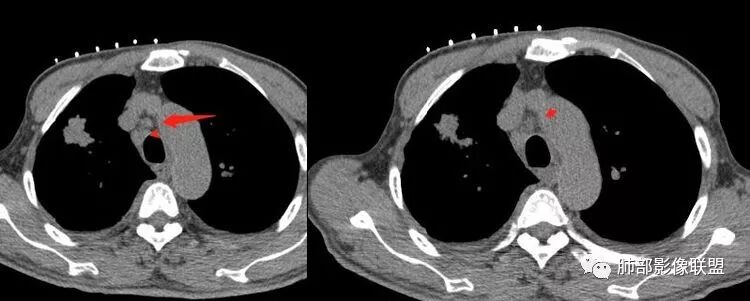

南边:纵隔淋巴结有融合的迹象,边界不清,右侧内乳动脉增粗了很多;怀疑纵隔淋巴结用血很大。有结核的话并不代表不能得癌肿;一般情况下结核附近的病灶呈条索树芽状;综上所述恶性不能完全排除。

2.右肺上叶斑片影、结节影、硬树丫,密度均匀未见钙化或液化。近胸壁处见分叶结节影及棘状突起,胸膜牵拉凹陷。

这种纵隔右移提示病程较长,腔静脉后见轻度增大淋巴结。

3.近胸壁处边缘分叶结节影,胸膜凹陷等使人怀疑基础疾病上出现新生物的可能性。

4.细看病灶有些散,有堆砌感。注意结核灶也常有胸膜牵拉。